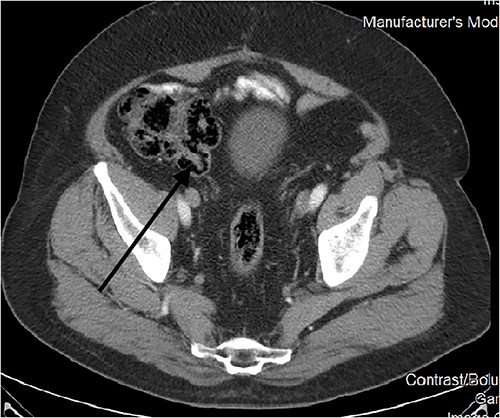

Our patient had a follow-up regimen of colonoscopies and CT scans for his colon cancer. The first mention of an inverted appendix was on his first postoperative colonoscopy in February 2005. It was also subsequently identified in further colonoscopies in years 2007, 2012 (where it was biopsied and revealed appendix mucosa), 2017, and 2023 (Fig. 1).

Endoscopically, it appears as a tubular elongated polypoid structure arising from the appendiceal orifice [11, 12]. Endoscopists can be reluctant to rule out neoplastic findings without a histological confirmation (such was the case in our patient’s 2012 colonoscopy). On CT scans, it appears as an elongated structure with a layered appearance at the appendiceal orifice. The presence of feces in the cecum might make diagnosis difficult [13].